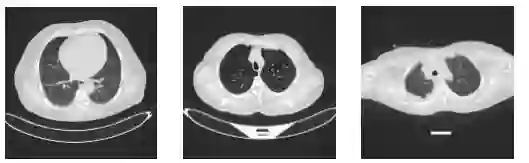

Early detection of lung cancer is critical to improving survival outcomes. We present a deep learning framework for automated lung cancer screening from chest computed tomography (CT) images with integrated explainability. Using the IQ-OTH/NCCD dataset (1,197 scans across Normal, Benign, and Malignant classes), we evaluate a custom convolutional neural network (CNN) and three fine-tuned transfer learning backbones: DenseNet121, ResNet152, and VGG19. Models are trained with cost-sensitive learning to mitigate class imbalance and evaluated via accuracy, precision, recall, F1-score, and ROC-AUC. While ResNet152 achieved the highest accuracy (97.3%), DenseNet121 provided the best overall balance in precision, recall, and F1 (up to 92%, 90%, 91%, respectively). We further apply Shapley Additive Explanations (SHAP) to visualize evidence contributing to predictions, improving clinical transparency. Results indicate that CNN-based approaches augmented with explainability can provide fast, accurate, and interpretable support for lung cancer screening, particularly in resource-limited settings.